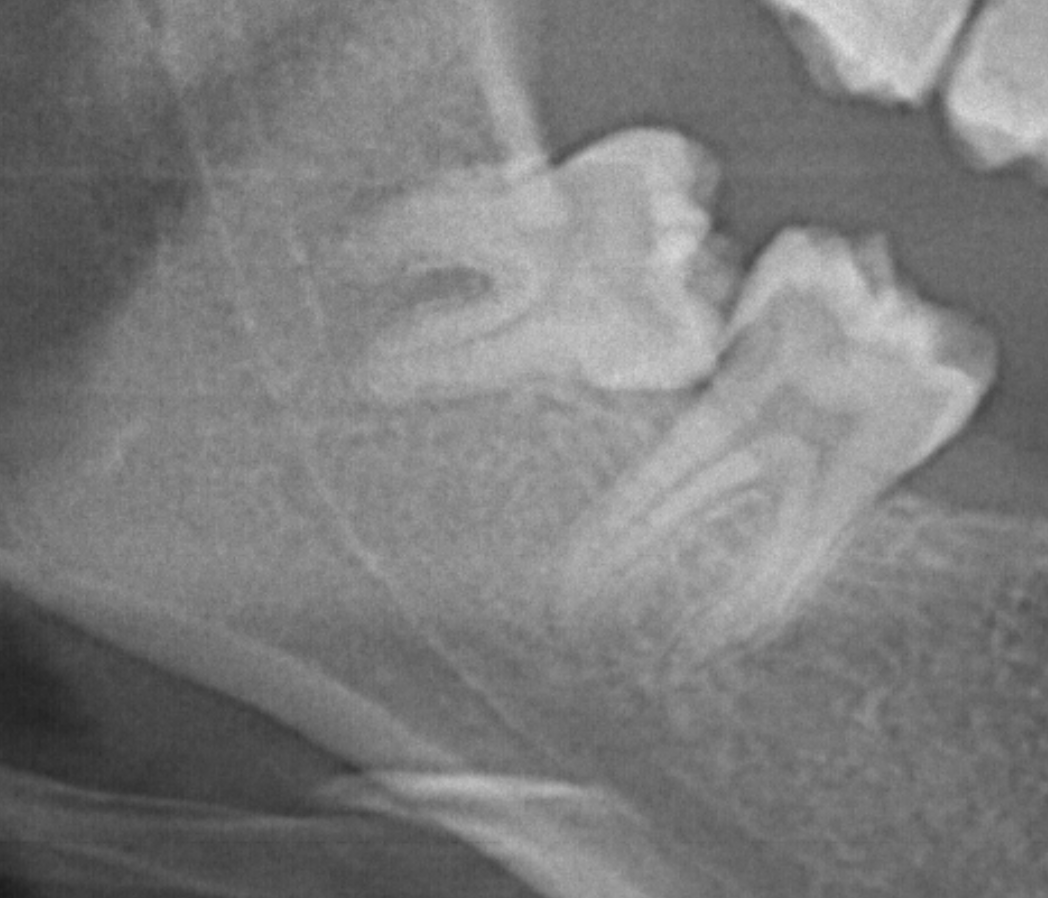

さて、今日は親知らず(下の歯)について記事にしていこうと思います。

たまに腫れたり、痛くなったりする下の親知らず、何が起こっているのでしょうか。

横向きに生えている親知らずは、上、下を問わずハブラシが到達しにくく、汚れがたまってしまいます。

横向きに生えている親知らずには歯間ブラシも糸ようじも通せないですから、ハブラシだけで戦わないといけないのですが、これではなかなか勝ち目はありません。